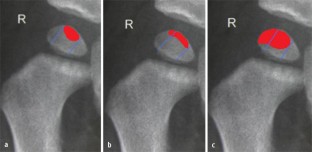

Abb. 3